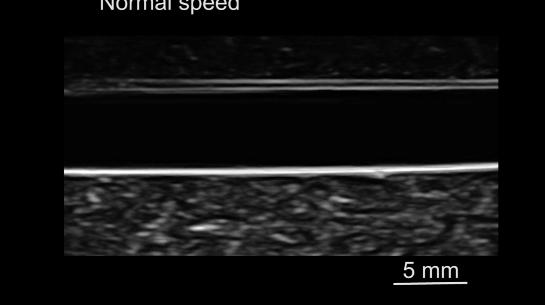

由于微型机器人在人体内的成像和导航是无线医疗机器人临床应用中的一个关键挑战,研究人员使用了超声设备,将磁驱软体鱼放置在血管模型内,使用超声设备对软体鱼进行成像和监测,并由频率为30赫兹、振荡角度为30°的振荡磁场驱动。

从下图可以看出,磁驱软体鱼可以在超声成像下游过血管。

图12.超声波引导磁驱软体鱼运动。